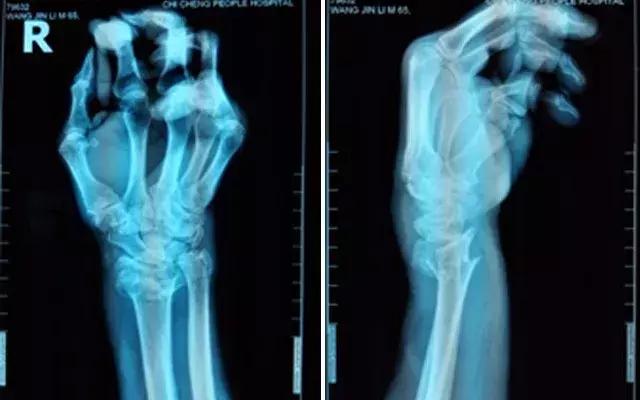

不稳定性骨折就是指骨折端易移位或复位后易再移位者,如斜形骨折、螺旋形骨折、粉碎性骨折、多段骨折、严重的椎体压缩性骨折、合并关节脱位的骨折等。它的特点是:固定后维持复位比较困难,很容易发生再次移位,导致发生畸形愈合。医生会给予患者严格的复位石膏固定,而且需严格按时定期复查,密切视察骨折断端移位情况。如果发生移位,就需要再次复位或手术治疗。常见的如尺桡骨骨折、第一掌骨基底骨折合并腕掌关节脱位等。

张大爷的骨折就属于不稳定的桡骨远端粉碎性骨折,早期虽然复位很好,但是随着患区组织肿胀的减轻,石膏就会出现松动,那么因为骨折端不稳定,复位可能就会出现不同程度的丢失,如果在不可接受范围,而这个时候可能已经错过了手法复位的理想时期,就基本需要手术复位了。